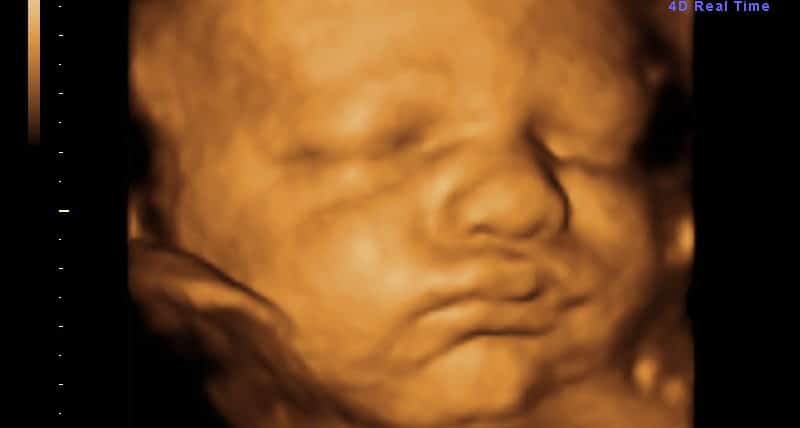

Seu bebê está praticamente pronto para nascer! Com cerca de 2,7 quilos e medindo entre 45 e 48 centímetros, ele já atingiu um tamanho considerável e seus sistemas estão funcionando de forma coordenada. A maioria dos órgãos, incluindo os sistemas circulatório e músculo-esquelético, está preparada para a vida fora do útero.

Nesta semana, a gordura continua se acumulando, especialmente preenchendo os ombros e joelhos do bebê, além de formar dobrinhas características no pescoço e na cintura. Essas reservas de gordura são fundamentais para regular a temperatura corporal após o nascimento. As gengivas estão endurecendo progressivamente, preparando-se para a futura erupção dos primeiros dentinhos.